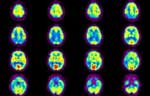

Αντιϋπερτασικοί παράγοντες συντελούν στην πρόληψη και αναστολή της προόδου της νόσου Αλτσχάιμερ

Λονδίνο: Οι αναστολείς του υποδοχέα της αγγειοτενσίνης που χορηγούνται για τη μείωση της αρτηριακής πίεσης μπορεί να συντελούν στην πρόληψη ή καθυστέρηση χιλιάδων περιπτώσεων νόσου Αλτσχάιμερ, σύμφωνα με αμερικανική μελέτη που δημοσιεύεται στο Διεθνές Συνέδριο για τη Νόσο Αλτσχάιμερ, στο Σικάγο.